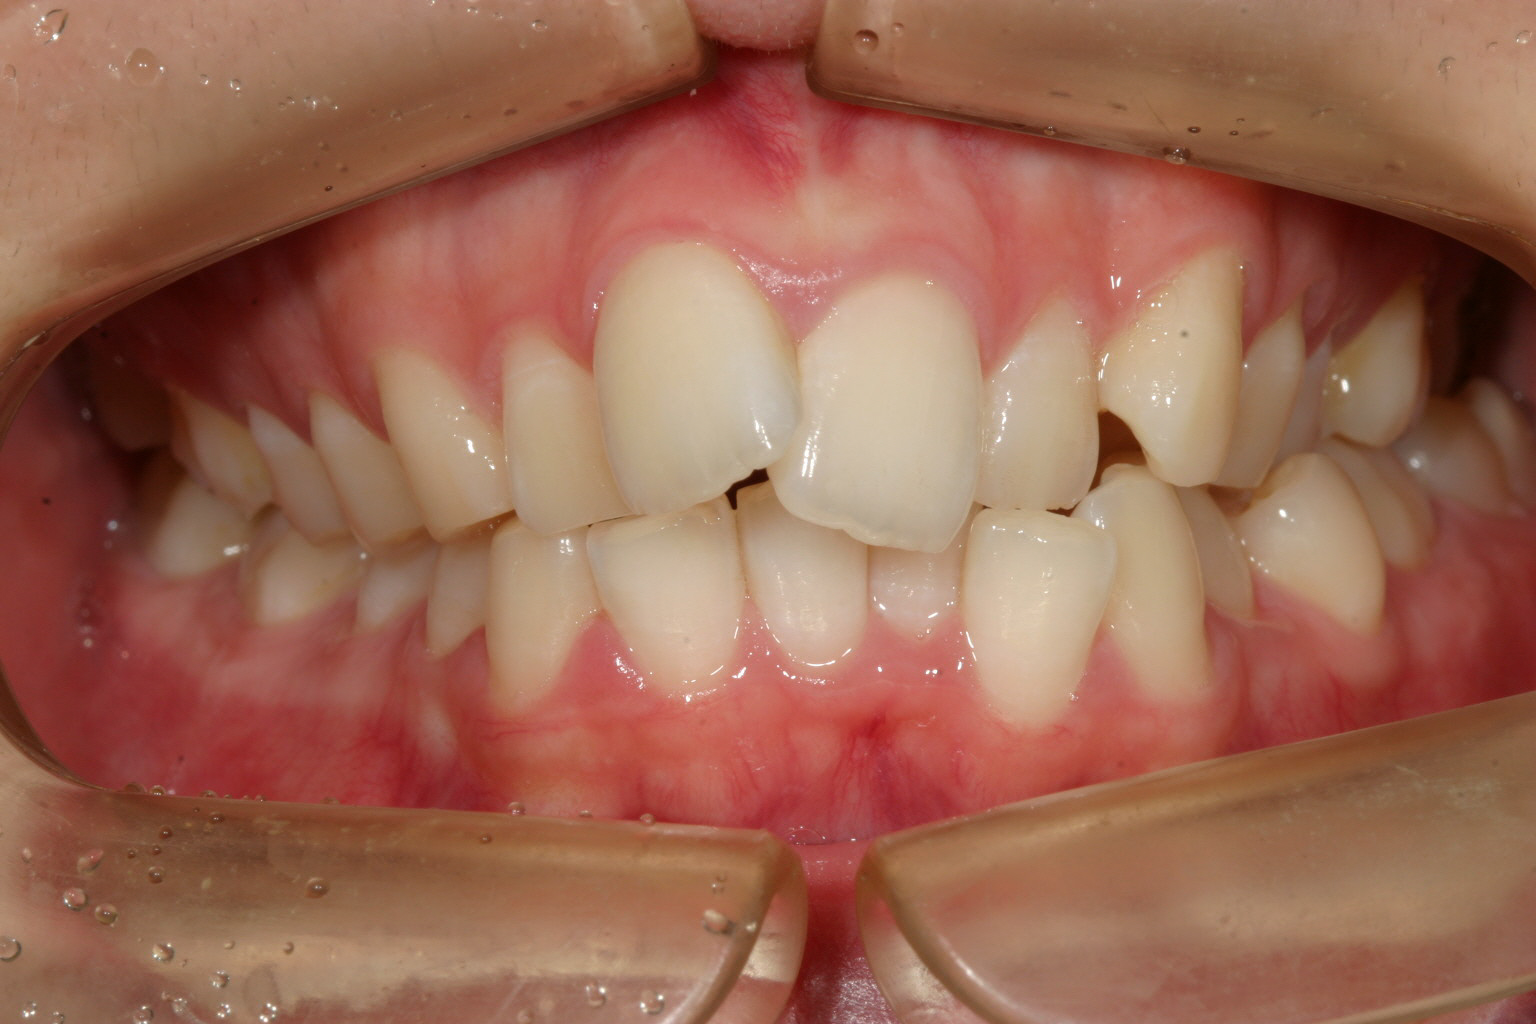

歯列がV字型になってます。

上の歯列がV字型ですから下顎もV字型です。

側面観もかなり飛び出してます。